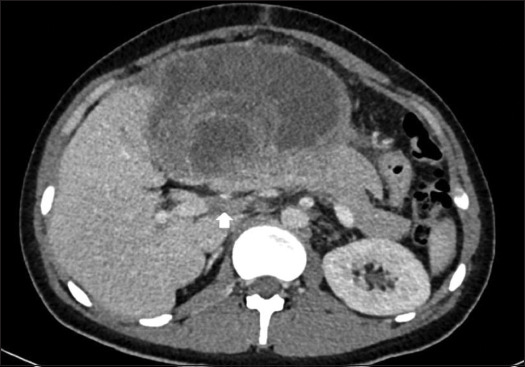

Case description: A 20-year-old boy with a large palpable abdominal mass, shortness of breath, and weight loss presented to our clinic. His computed tomography scan showed showed a large cystic lesion measuring 11.5 × 22.7 × 23 cm, predominantly involving the left lobe and right anterior sector, with a biopsy consistent with UESL. The tumor was abutting to the right hepatic vein, with bland main portal vein thrombosis. Due to an irresectable tumor and deteriorating clinical condition, living donor LT was performed. The patient remains in good health at 16 months of follow-up.